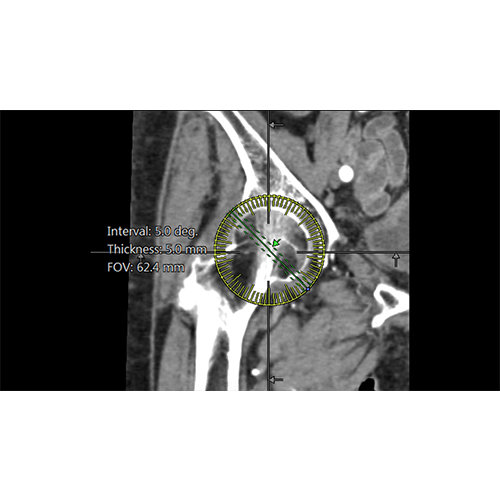

ANYTHINK 经导管主动脉瓣膜置换术分析系统